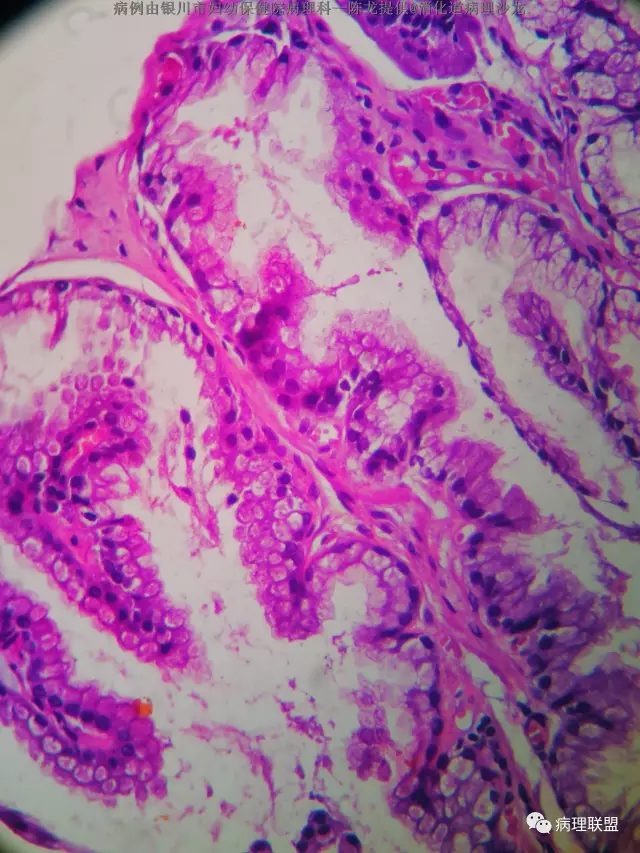

男性 68 十二指肠息肉 大小约3个0.4

(病例由银川市妇幼保健院病理科—陈龙提供,致谢!)